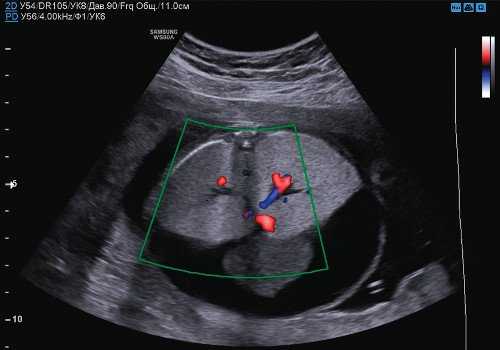

Следующим этапом была оценка голосовых связок на УЗИ. Для этого было проведено сканирование в корональной плоскости на уровне шеи плода, что позволило визуализировать трахею, гортань и голосовые связки. Мы систематически оценивали анатомические данные и функциональные возможности, включая нормальный вид; оценивали движения открытия-закрытия голосовых связок в трахею; прохождение жидкости через трахею с помощью цветной допплерографии (рис. 1).

Рис.1. Корональный срез шеи плода на уровне трахеи, который показывает нормальный внешний вид гортани и голосовых связок с нормальным открытием (а) и закрытием (б) просвет трахеи при прохождении жидкости. Изображения (с) (d) движения жидкости по трахеи с использованием цветного допплера.